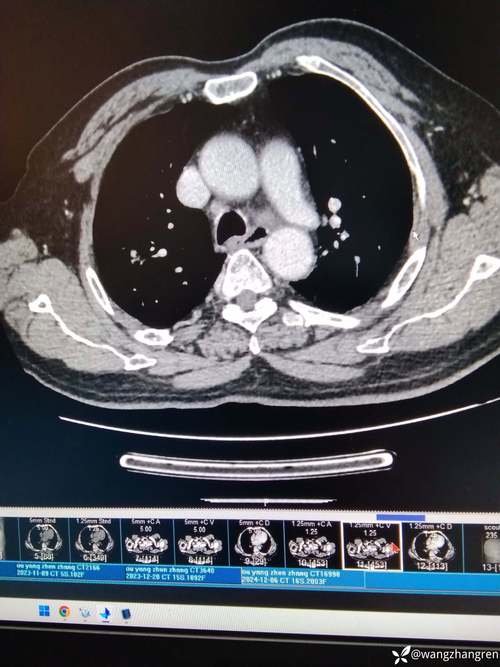

影像诊断区块链就是利用区块链技术,为医学影像(如CT、MRI、X光片等)及其诊断报告的生成、存储、传输、使用全过程建立一个去中心化、安全、透明、不可篡改的信任网络。